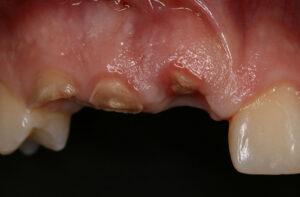

Hier sieht man das Problem:

Unfall – Durch einen Unfall sind die rechten oberen Schneidezähne sowie der Eckzahn massiv beschädigt worden. Alle drei Zähne sind nicht erhaltungsfähig.